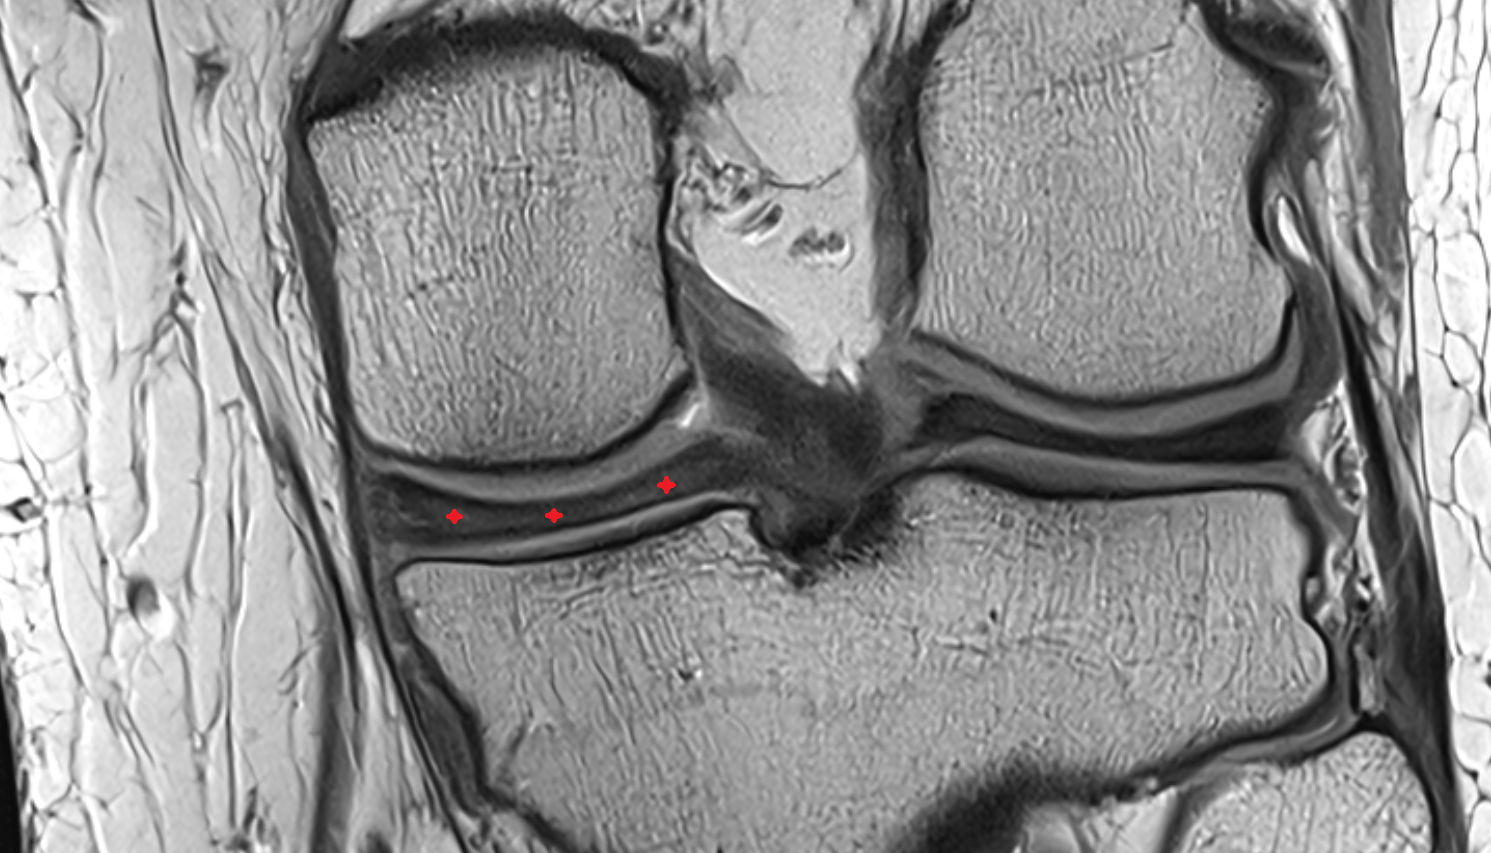

- Medial meniscus

- Lateral meniscus

- Anterior horn of medial meniscus

- Posterior horn of medial meniscus

- Body of medial meniscus

- Anterior root of medial meniscus

- Posterior root of medial meniscus